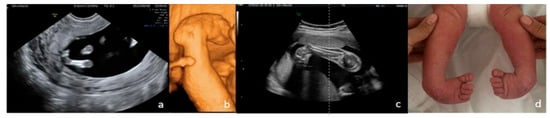

Postnatal diagnoses confirmed that the most frequent anomaly was clubfoot (40.58%) [Figure 6], followed by limb reduction defects (20.29%) [Figure 7], polydactyly (13.04%), shortened/angulated bones (10.15%), joint contracture/abnormal position (10.15%), others (4.35%) and syndactyly (1.44%).

Figure 6. Bilateral clubfoot. (a)—2D FT anomaly scan, showing the abnormal angle of the left foot (both feet seemed rotated inward). (b)—3D surface rendering applied at ST anomaly scan, confirming the clubfoot suspicion. (c)—2D third-trimester image of the right foot (both feet rotated inward). (d)—postnatal aspect.

Figure 7. Upper-limb unilateral (left) reduction defect. In this case, of transverse limb deficiency, the defect was diagnosed at the end of the first trimester. Complete genetic work-up was performed, rendering normal results; the follow-up scans strengthened the suspicion of isolated anomaly, and the parents decided to continue pregnancy. (a)—postnatal aspect. (b)—radiography confirming the presence of the well-developed humerus and rudimentary buds of the radius and ulna. Multidisciplinary counseling was offered repeatedly, and led to surgical reconstruction and prosthetics, with good functional results.